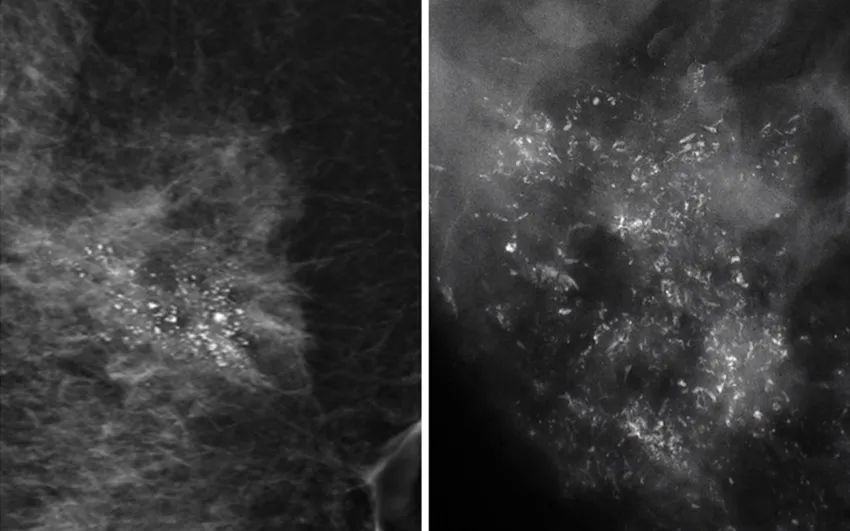

?我們在檢查時(shí)如何判斷是良性鈣化點(diǎn)呢?

一般來說,若鈣化點(diǎn)比較大顆,沒有群聚簇集的特性,形狀外觀的界線清楚明確,長的均勻、對稱,就屬于良性鈣化點(diǎn)的特征。

乳房的鈣化點(diǎn)大部分都是良性的,或伴有其他良性病變,如乳腺增生。所以,乳房鉬靶上如果看到大大的白點(diǎn),通常就是良性鈣化點(diǎn),如纖維腺瘤就常常會在鉬靶的影像上出現(xiàn)爆米花狀的粗糙大白點(diǎn)。

2.惡性鈣化

當(dāng)癌細(xì)胞不受控制地生長,這一群癌組織會變得很擁擠,導(dǎo)致里面小部分的細(xì)胞會因組織缺氧而壞死。這時(shí),我們身體無法清除壞死的組織,這些細(xì)胞就變硬而形成鈣化點(diǎn)。

因此,惡性鈣化點(diǎn)的特點(diǎn)是:聚集很緊密,簇聚于局部區(qū)塊,且鈣化點(diǎn)很小,形狀不規(guī)則,每個(gè)點(diǎn)都不太一樣,或有針尖狀、小桿狀、分叉狀、簇狀及泥沙樣多屬于惡性病變。